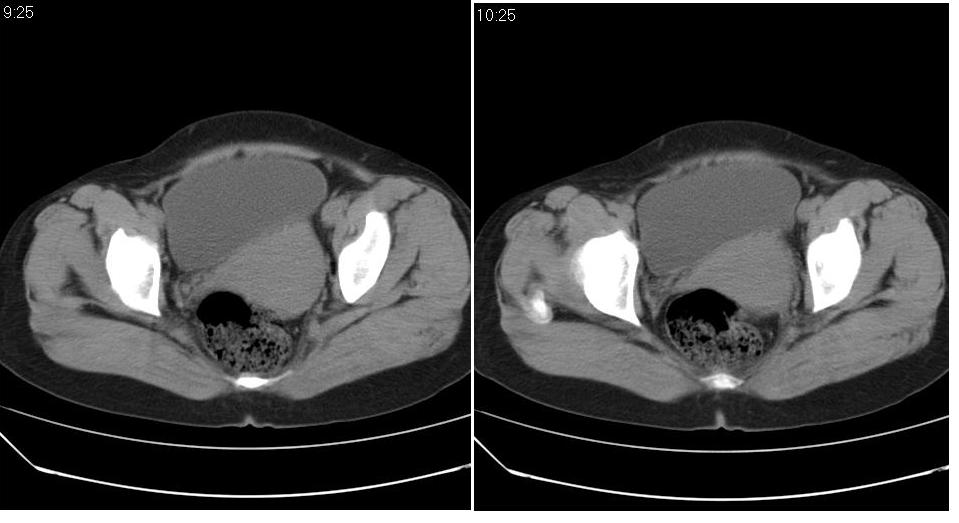

女 35岁,下腹部坠感疼,其它病史不详。图象顺序有点乱。

定位于盆腔附件,有囊性密度,有脂肪密度、还有骨密度;应该是比较典型的卵巢畸胎瘤。